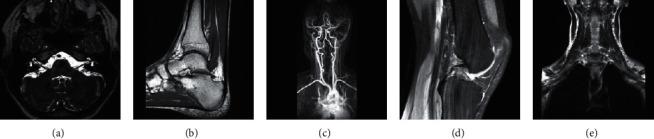

Magnetic resonance imaging has significant applications for disease diagnosis. Due to the particularity of its imaging mechanism, hardware imaging suffers from resolution and reaches its limit, and higher radiation intensity and longer radiation time will cause damage to the human body. The problem is expected to be solved by a superresolution algorithm, especially the image superresolution based on sparse reconstruction has good performance. Dictionary generation is a key issue that affects the performance of superresolution algorithms, and dictionary performance is affected by dictionary construction parameters: balance parameters, dictionary size, overlapping block size, and a number of training sample blocks. In response to this problem, we propose an optimal dictionary construction parameter search method through the experiment to find the optimal dictionary construction parameters on the MR image and compare them with the dictionary obtained by multiple sets of random dictionary construction parameters. The dictionary we searched for the optimal parameters of the dictionary construction training has more powerful feature expressions, which can improve the superresolution effect of MR images.